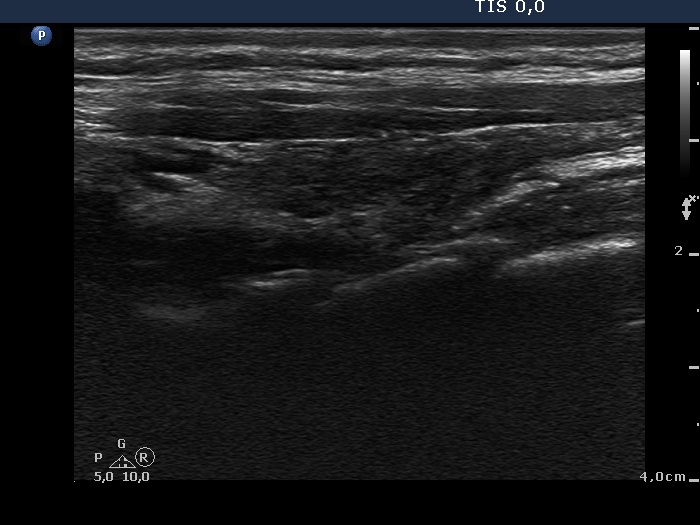

One year after radioiodine therapy (third row):

Clinical presentation: the patient had no complaints.

Palpation: the thyroid could not be palpated.

Functional state: mild hypothyroidism on daily 112.5 microgram levo-tiroxine (TSH-level 5.11 mIU/L).

Ultrasonography: the thyroids were hypoechogenic and presented extensive fibrosis. The size of the lobes decreased significantly. The thyroid presented no and decreased vascularization, right and left lobe, respectively.

Suggestion to increase the dose of levo-tiroxine to daily 125 microgram.